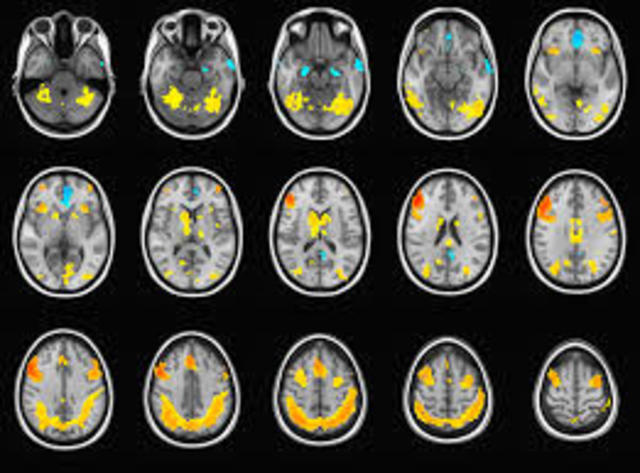

1) Surgimiento de las imágenes cerebrales.

La incorporación y difusión de las técnicas imagenológicas contemporáneas, en especial la escanografía cerebral o la tomografía axial computarizada (TAC), implicó una verdadera revolución en todas las ciencias neurológicas.

• fMRI y PET

fMRI y PET

Durante la década de 1990 se fortalece la investigación con el empleo de imágenes no ya anatómicas sino funcionales, en particular la resonancia magnética funcional (fMRI, por sus siglas en inglés) y la tomografía por emisión de positrones (PET), que han permitido visualizar la actividad cerebral durante la realización de diferentes tareas cognoscitivas (por ejemplo, hablar, leer, pensar en palabras, etc.).